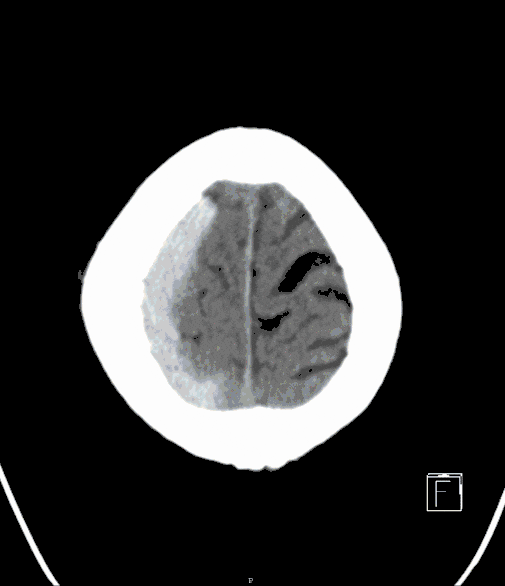

Depending on the severity of the injury, potentially life-threatening situations may arise from increased pressure within the cranial cavity, requiring surgery as a last resort in certain circumstances. In other cases, immediate surgery may be required first (impression fractures, epidural and subdural hemorrhages).